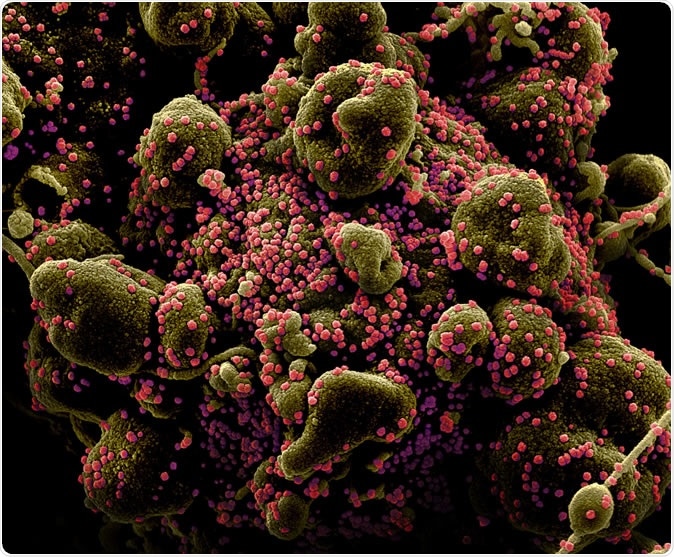

Novel Coronavirus SARS-CoV-2 Colorized scanning electron micrograph of an apoptotic cell (greenish brown) heavily infected with SARS-COV-2 virus particles (pink), isolated from a patient sample. Image captured and color-enhanced at the NIAID Integrated Research Facility (IRF) in Fort Detrick, Maryland. Credit: NIAID